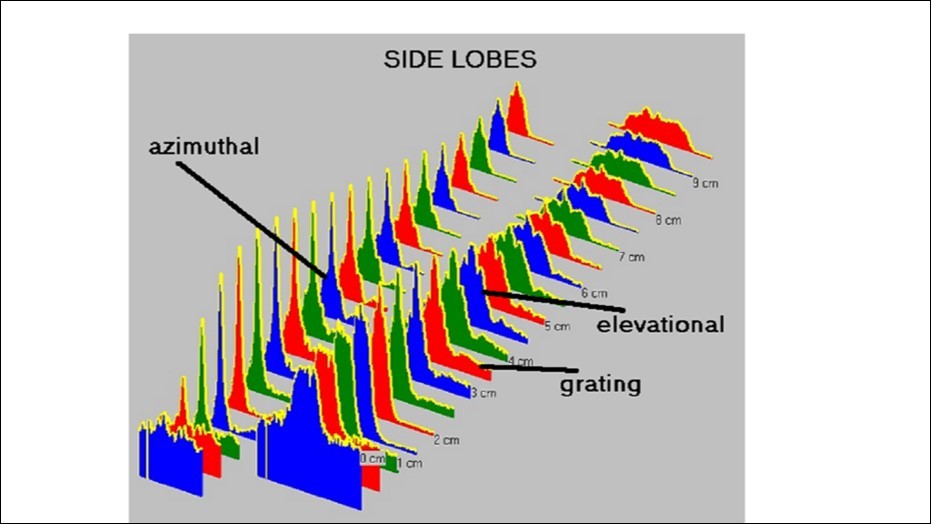

Maximum acoustic contrast and grayscale resolution of the various ultrasound probes was evaluated with software from Tissue Characterization Consulting (TCC), Figure 2. The higher and narrower the amplitude, the sharper the acoustic contrast 6, 8, 9.

Acoustic contrast, using the RVP, was documented with linear arrays and matrix transducers. Low intensity contrast differences are indistinguishable and appear nearly black to the naked eye because the human eye can only discern 16 gray levels. These small differences in the low intensity range can however be visualized and evaluated when projected onto the 8-bit grayscale (256 shades of gray) of modern equipment. This is possible when the dynamic range (DR) is properly set and results in a smooth contrast graph, Figure 2.

Figure 2.measurement side lobes in different depths. A high and narrow amplitude indicates a sharp acoustic contrast. (azimuthal = lateral; elevational = perpendicular to lateral = transversal)